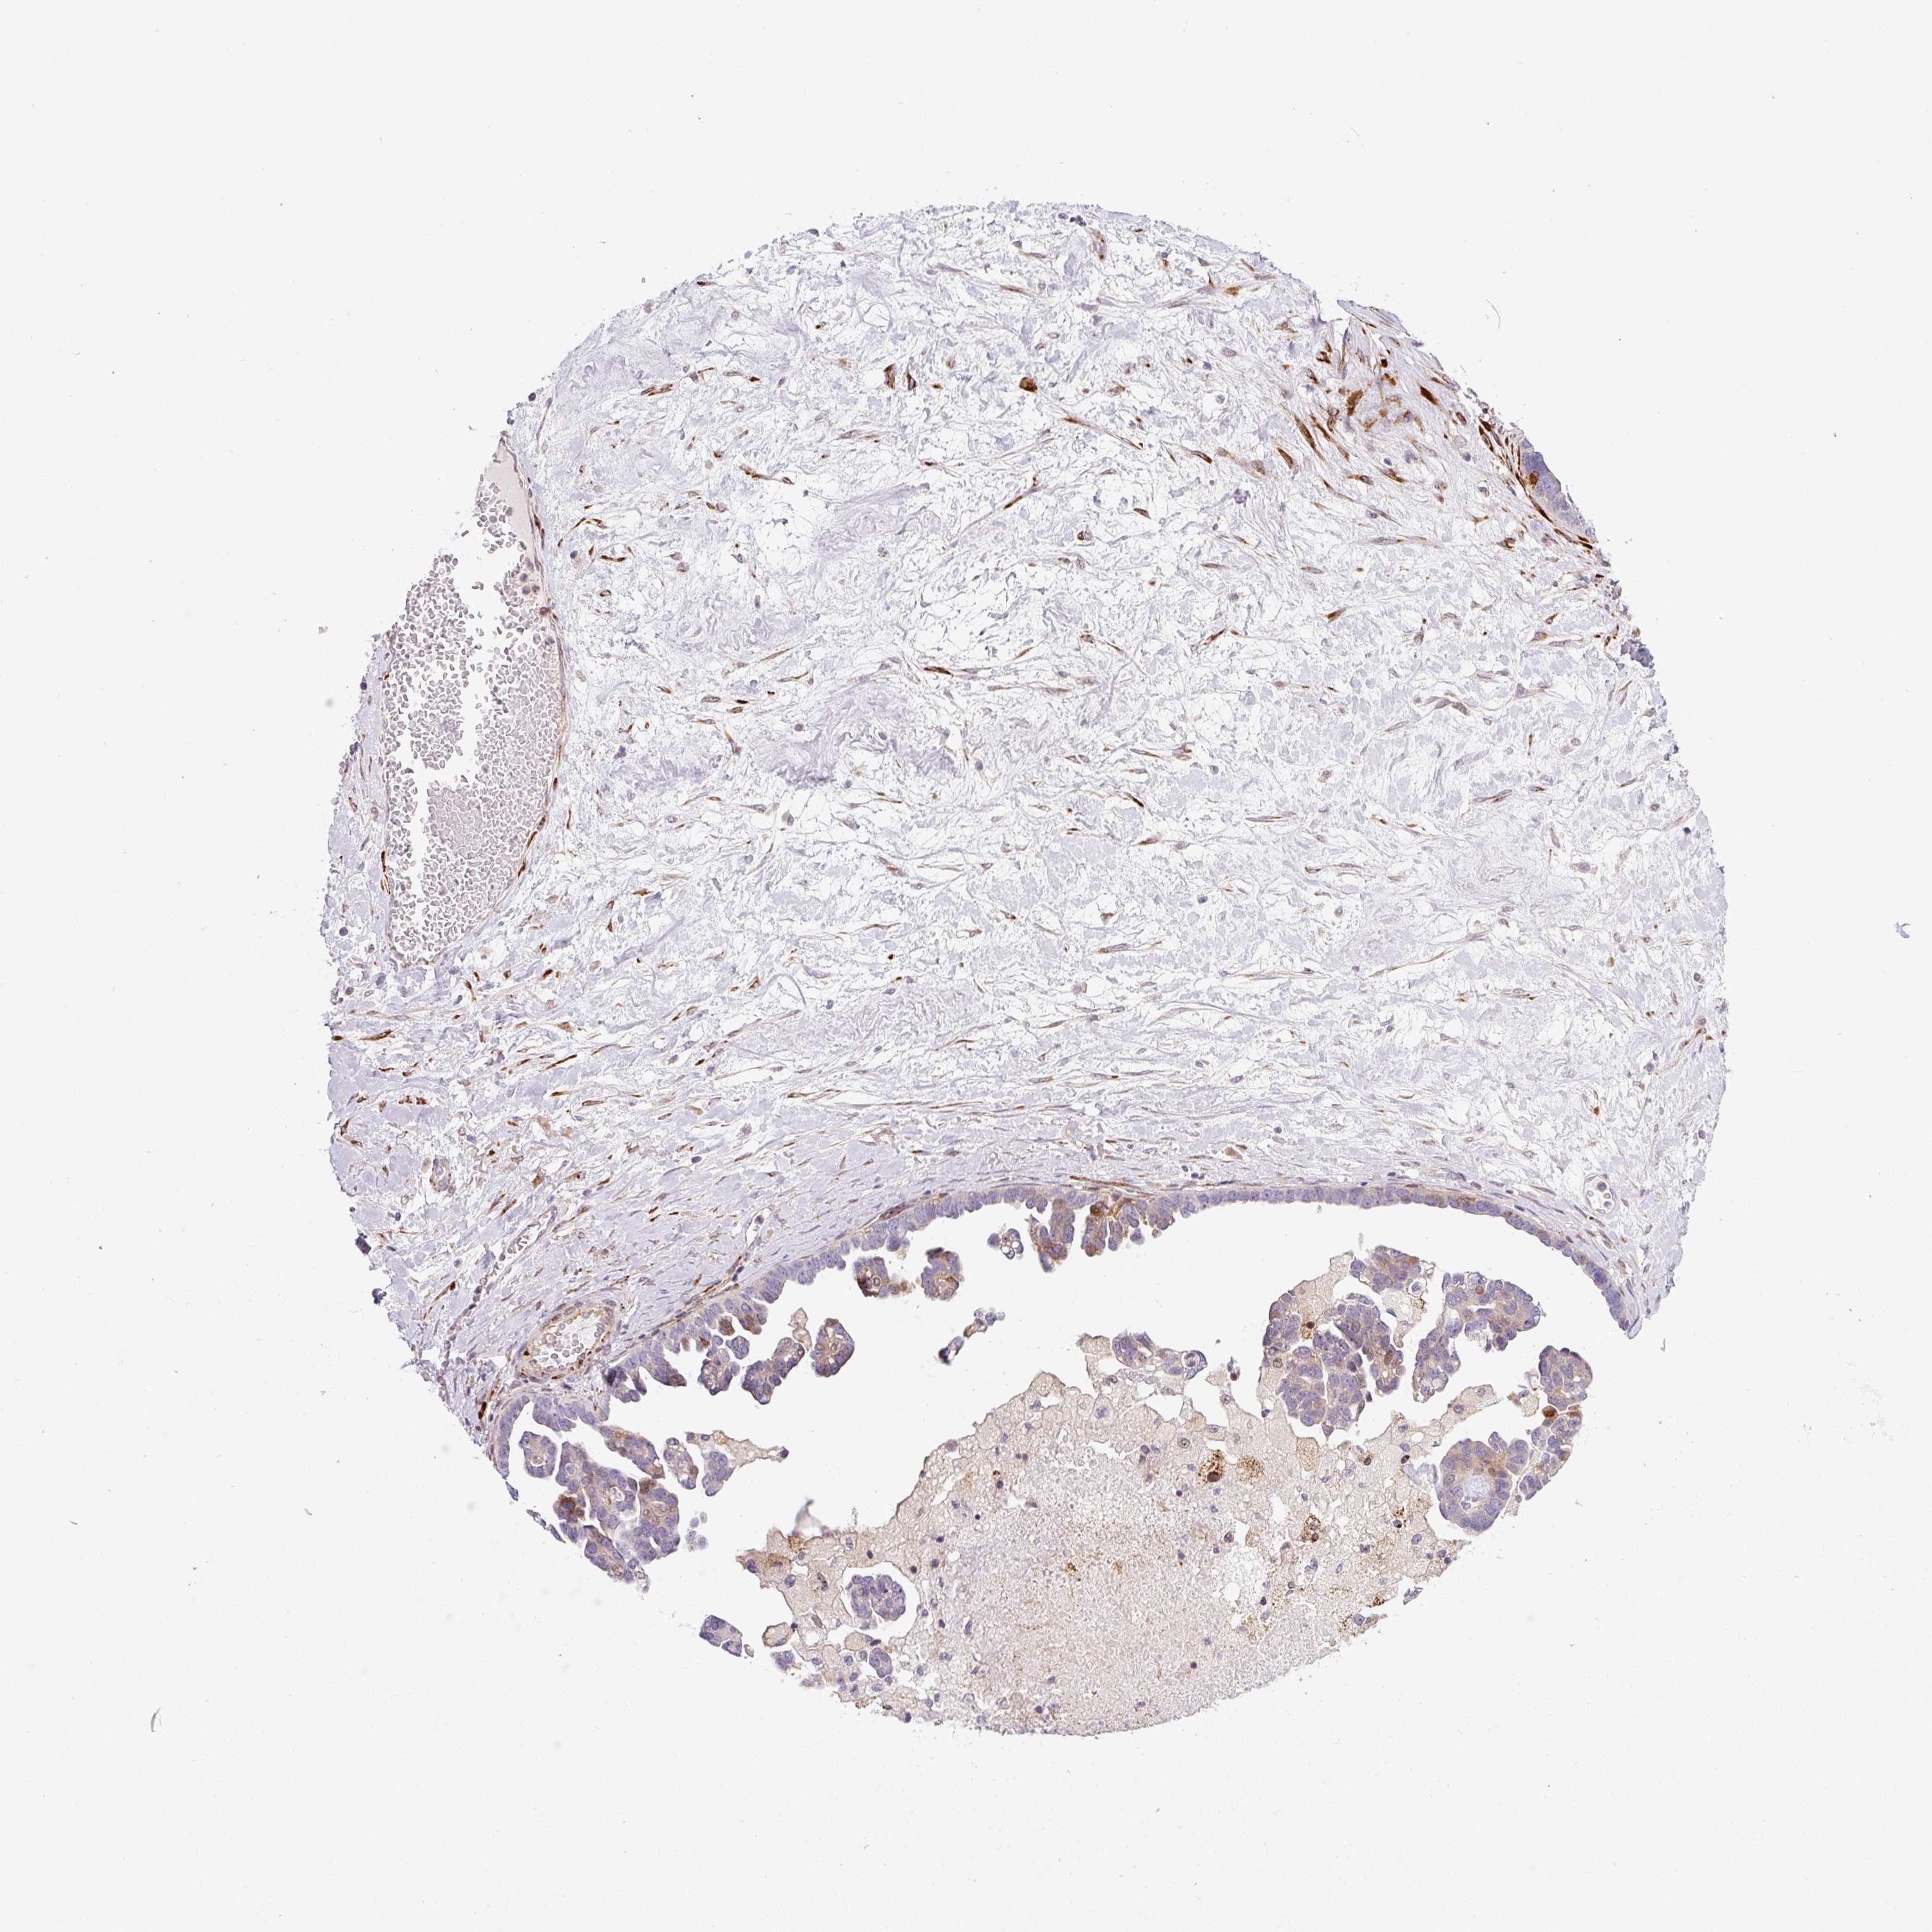

OVARIAN CANCER - Protein expressioni

A mouse-over function shows sample information and annotation data. Click on an image to view it in a full screen mode. Samples can be filtered based on level of antibody staining by selecting one or several of the following categories: high, medium, low and not detected. The assay and annotation is described here.

Note that samples used for immunohistochemistry by the Human Protein Atlas do not correspond to samples in the TCGA dataset.

Antibody stainingi

Antibody staining in the annotated cell types in the current human tissue is reported as not detected, low, medium, or high, based on conventional immunohistochemistry profiling in selected tissues. This score is based on the combination of the staining intensity and fraction of stained cells.

Each image is clickable and will lead to virtual microscopy that enables deeper exploration of all samples and also displays staining intensity scores, fraction scores and subcellular localization as well as patient and tissue information for each sample.

Antibody HPA054579

Staining

High

Medium

Low

Not detected

Intensity

Strong

Moderate

Weak

Negative

Quantity

>75%

75%-25%

<25%

None

Location

Nuclear

Cytoplasmic/membranous

Cytoplasmic/membranous,nuclear

Cystadenocarcinoma, serous, NOS

Carcinoma, endometroid

Cystadenocarcinoma, mucinous, NOS

Carcinoma, NOS